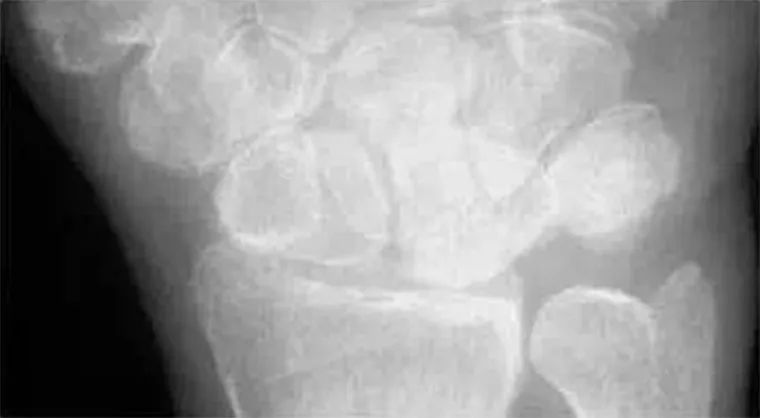

Analyze - 腕骨弧线正位弧线不连续,侧位明显脱位。

Case 分析

1.月骨-三角骨间隙不平行,存在重叠。

2.钩状骨和月骨也存在重叠。

3.桡骨、月骨、舟骨近极和头状骨近极平行关系存在。

4.三角骨、钩骨、头状骨远极、大多角骨和舟骨远极平行关系也存在。

5.头状骨和舟骨骨折。

诊断:经舟骨、经头状骨月骨周围骨折-脱位。